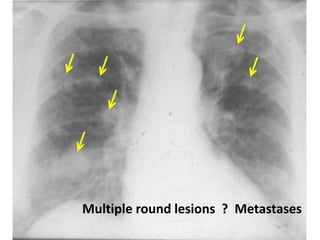

Multiple round lesions ? Metastases

metastasis

Metastases